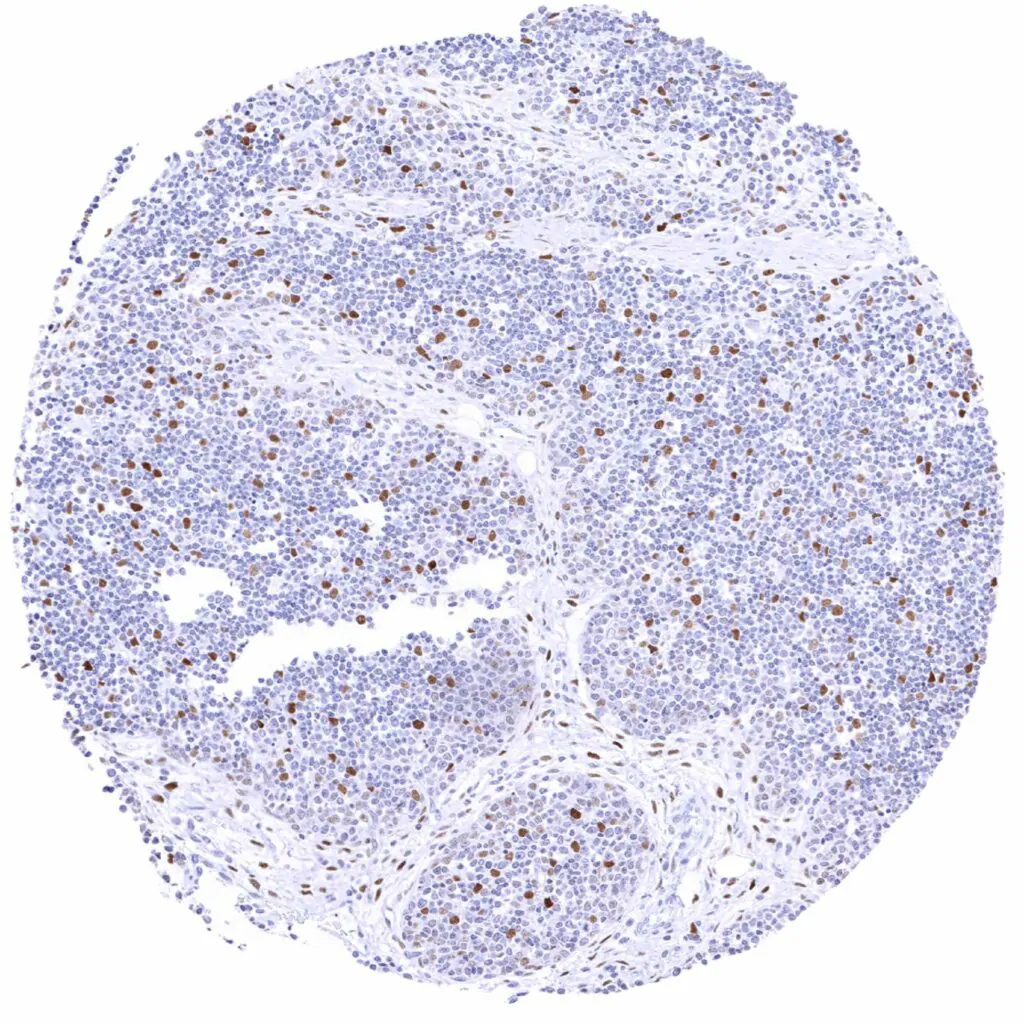

Spleen – Weak Cyclin E1 staining of only a small fraction of cells